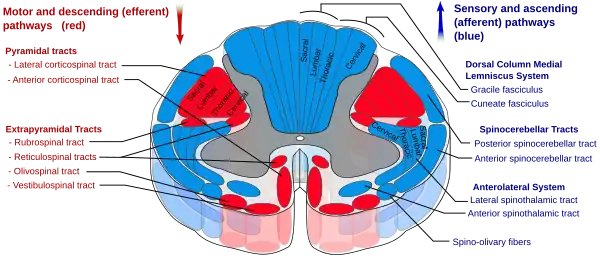

Nerve tracts

Nerve tracts are bundles of axons as white matter, that carry action potentials to their effectors. In the spinal cord these descending tracts carry impulses from different regions. These tracts also serve as the place of origin for lower motor neurons. There are seven major descending motor tracts to be found in the spinal cord:[16]

- Lateral corticospinal tract

- Rubrospinal tract

- Lateral reticulospinal tract

- Vestibulospinal tract

- Medial reticulospinal tract

- Tectospinal tract

- Anterior corticospinal tract